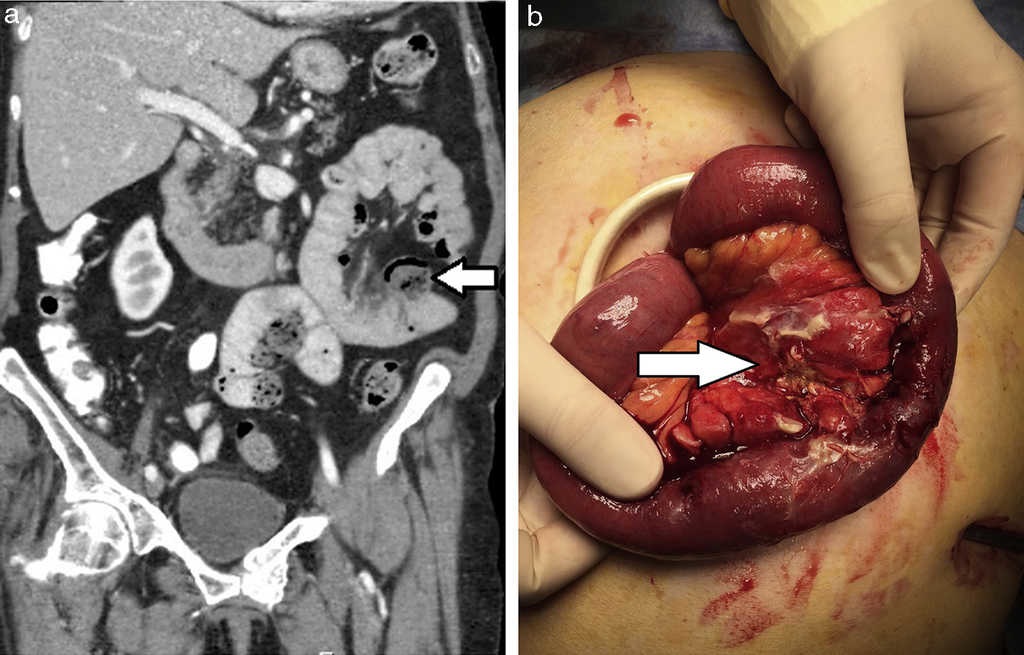

Diverticulitis y perforación (5%): se visualiza engrosamiento parietal y deformación de los contornos del divertículo complicado, con aumento de la densidad de los planos grasos adyacentes y formaciones ganglionares reactivas asociadas, generalmente en rango no adenomegálico. La TCMD descarta o confirma la existencia de colecciones abscedadas o de neumoperitoneo2 (figs. 2–5).